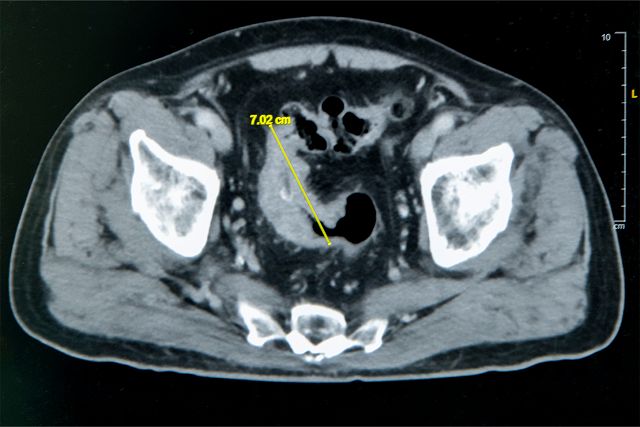

大腸直腸外科主任張譽耀醫師表示,老翁罹患乙狀結腸癌,腫瘤約7公分造成腸子幾乎完全阻塞,也導致老翁一進食就會肚子又脹又痛;術前因為不敢進食,老翁體重下降、營養不足,也可能造成傷口癒合不良。老翁的手術其實會有兩個傷口,一個是肚子上的傷口、一個腸子的傷口,若腸子傷口癒合不良會造成腸吻合滲漏,到時就必須做人工肛門了!所幸經過提早住院,透過靜脈營養針先建立營養,讓病人強健身體後才手術,術後傷口果然順利癒合。手術順利完成,老翁術後恢復良好,疼痛程度遠低於預期,他開心表示:「沒想到這麼快就能下床,真的很感謝醫師。」